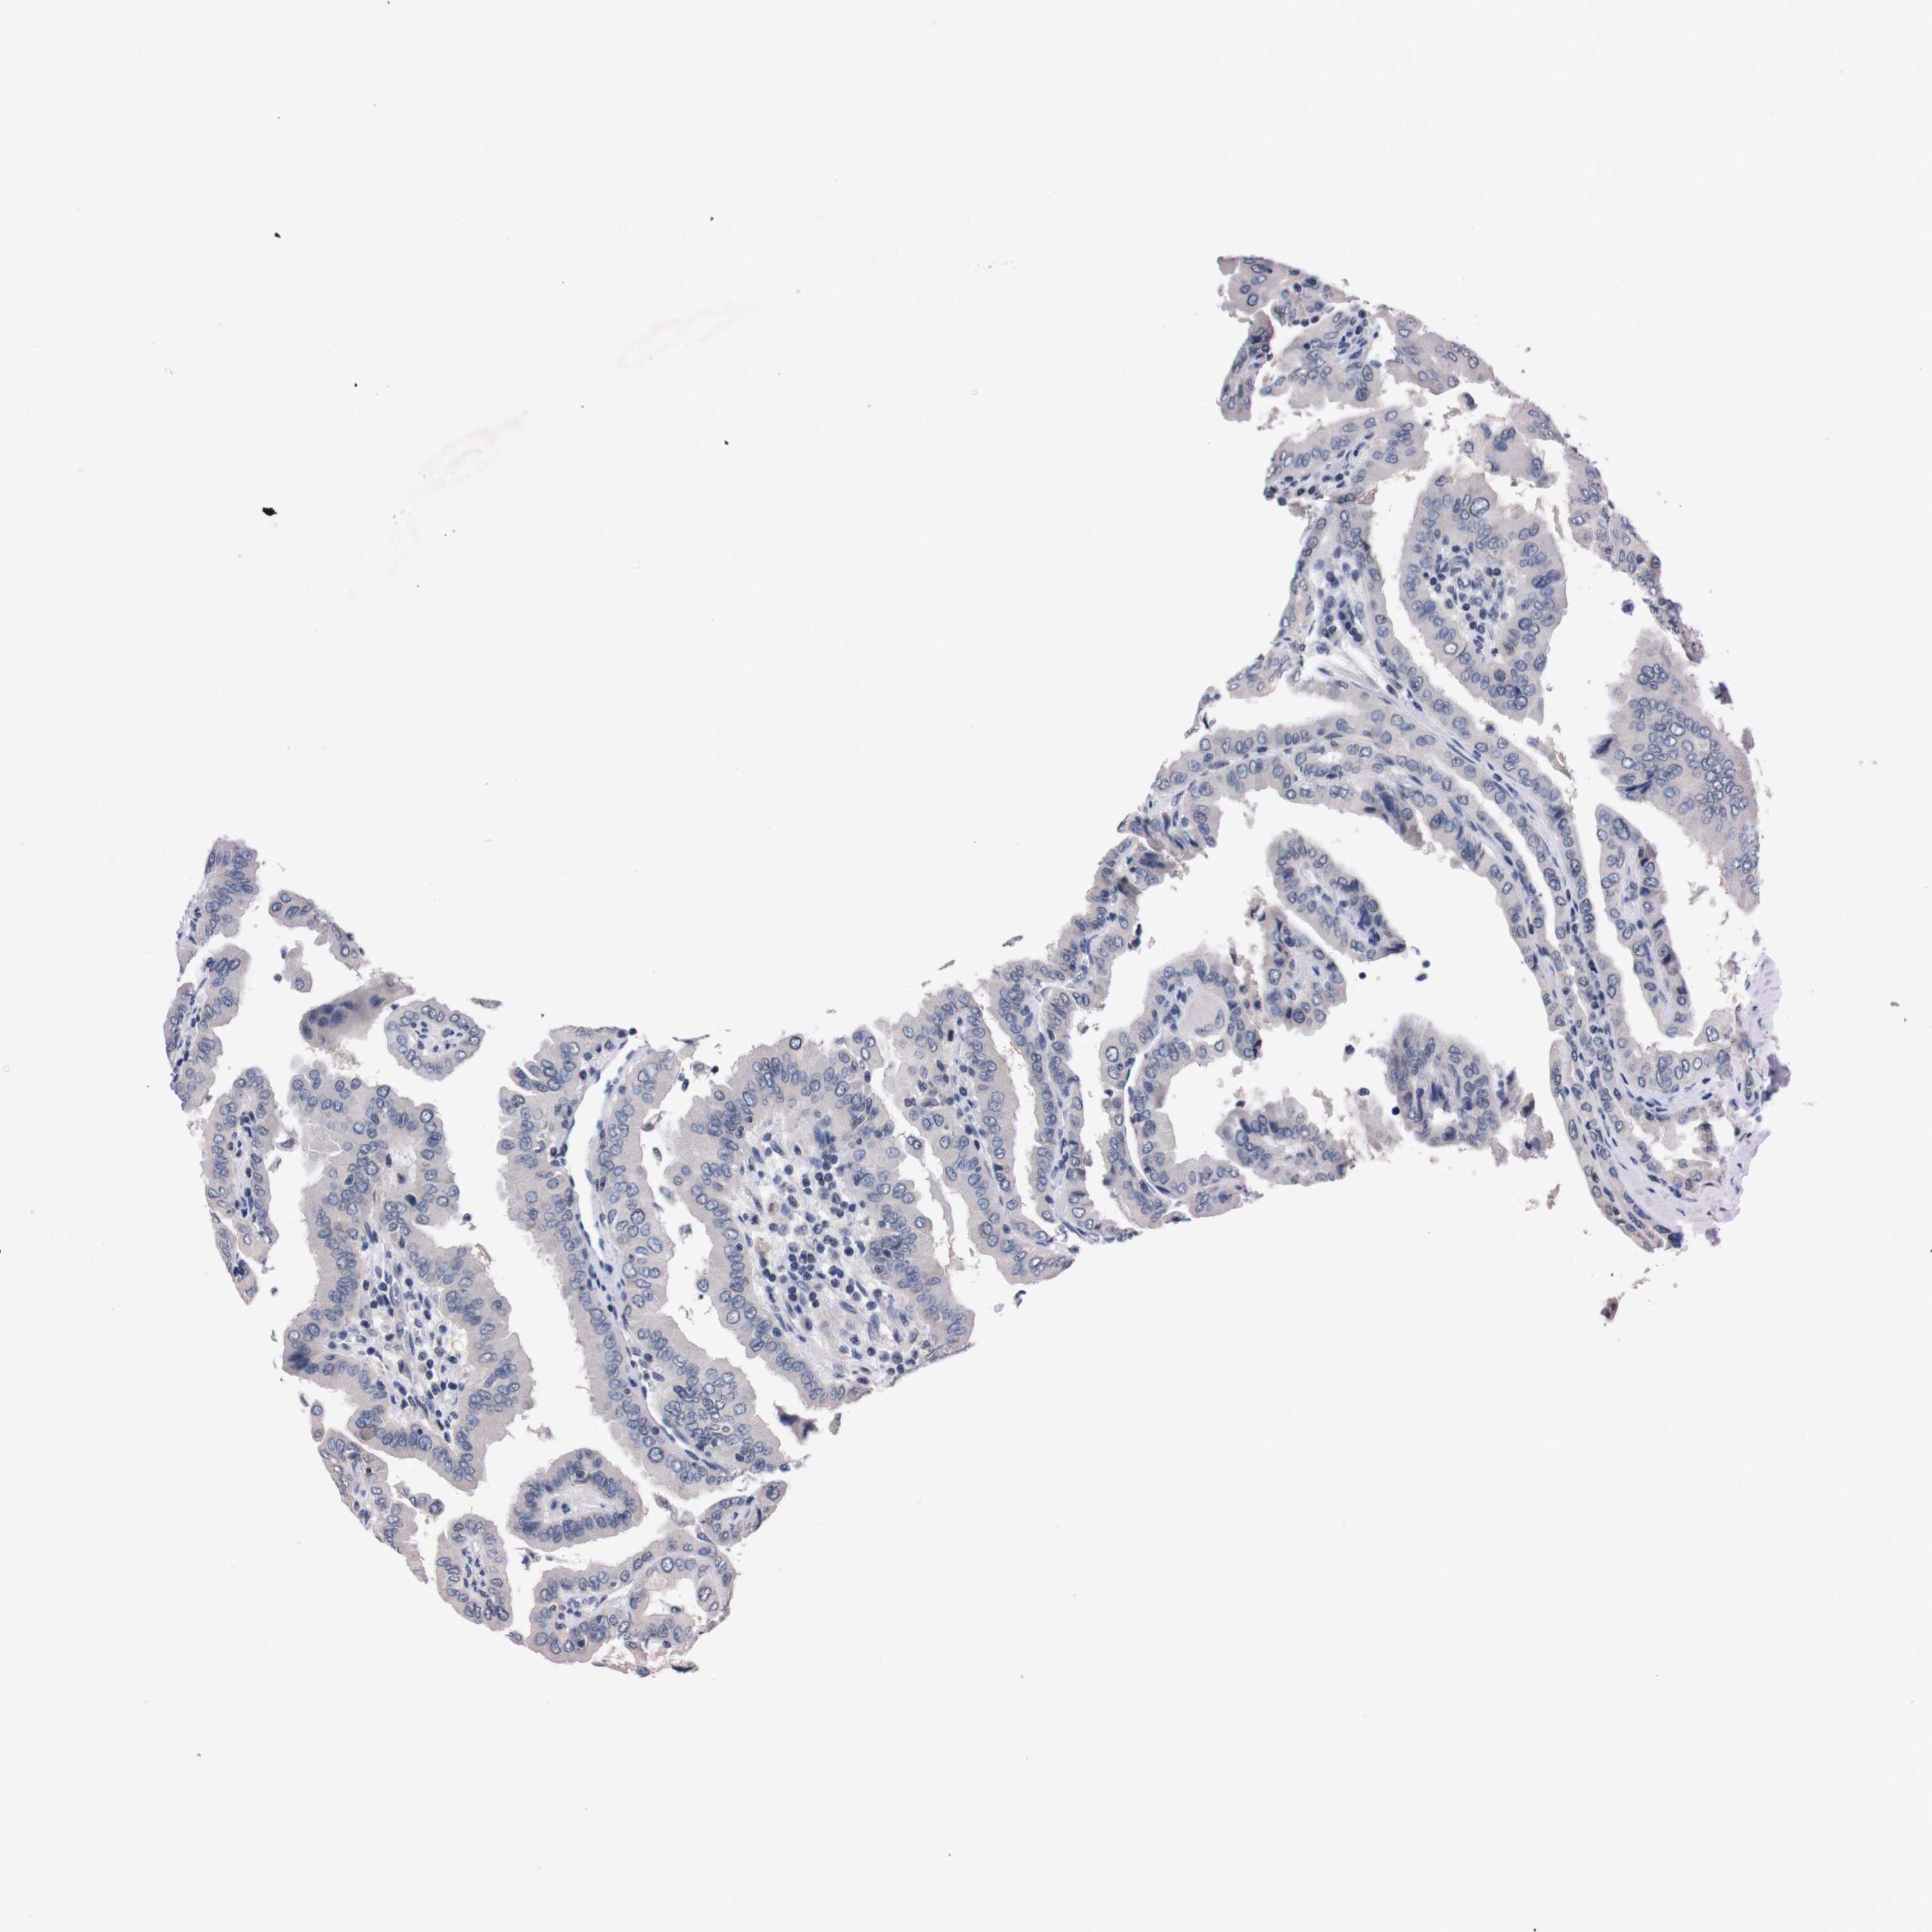

THYROID CANCER - Protein expressioni

A mouse-over function shows sample information and annotation data. Click on an image to view it in a full screen mode. Samples can be filtered based on level of antibody staining by selecting one or several of the following categories: high, medium, low and not detected. The assay and annotation is described here.

Note that samples used for immunohistochemistry by the Human Protein Atlas do not correspond to samples in the TCGA dataset.

Antibody stainingi

Antibody staining in the annotated cell types in the current human tissue is reported as not detected, low, medium, or high, based on conventional immunohistochemistry profiling in selected tissues. This score is based on the combination of the staining intensity and fraction of stained cells.

Each image is clickable and will lead to virtual microscopy that enables deeper exploration of all samples and also displays staining intensity scores, fraction scores and subcellular localization as well as patient and tissue information for each sample.

Antibody HPA006746

Antibody CAB009805

Staining

High

Medium

Low

Not detected

Intensity

Strong

Moderate

Weak

Negative

Quantity

>75%

75%-25%

<25%

None

Location

Nuclear

Cytoplasmic/membranous

Cytoplasmic/membranous,nuclear

Papillary adenocarcinoma, NOS

Follicular adenoma carcinoma, NOS